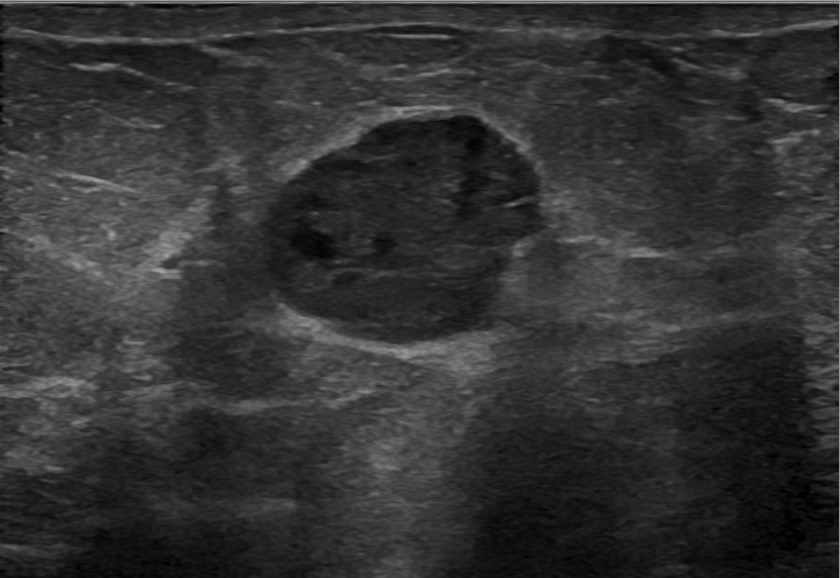

- No distinct imaging findings can distinguish between subtypes of papillary carcinomas (AJR Am J Roentgenol 2012;198:264, Front Surg 2022;8:743881)

- Imaging does not distinguish encapsulated papillary carcinoma (EPC) with and without invasion beyond the capsule (Breast J 2019;25:539, Breast J 2021;27:209)

- Ultrasound:

- Hypoechoic solid mass, sometimes with cystic component

- Color Doppler often highlights prominent vascular supply

Radiology images

Contributed by Mariel Molina Nunez, M.D. and Julie Jorns, M.D. (Case #518)

Images hosted on other servers: